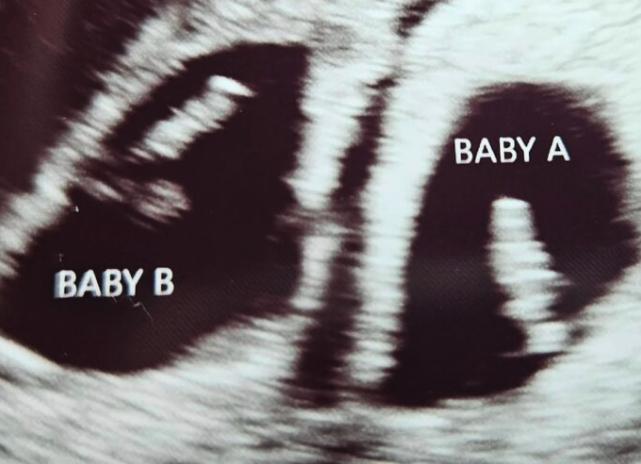

"It was a long process, but in September 2022, two of the embryos were twins, and they both took," Anna Ames told EastIdahoNews.com.

"We transferred (the embryo) on Feb. 9, 2025," Anna said, referring to the IVF transfer date – the specific day a fertilized embryo is placed into the uterus.